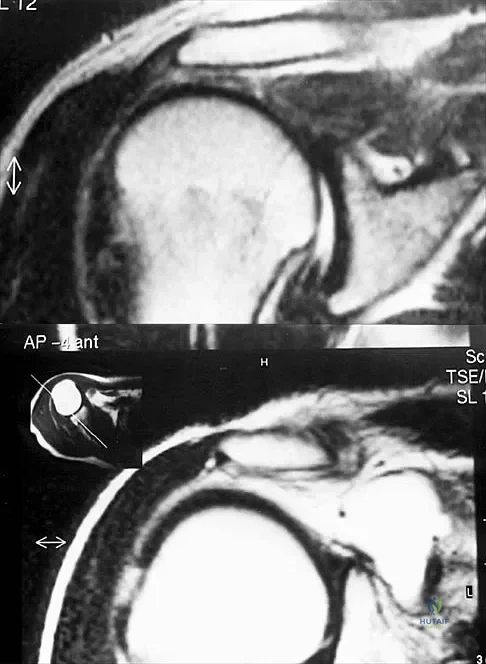

Figures 49a and 49b show MRI scans of the shoulder. What is the most likely diagnosis?